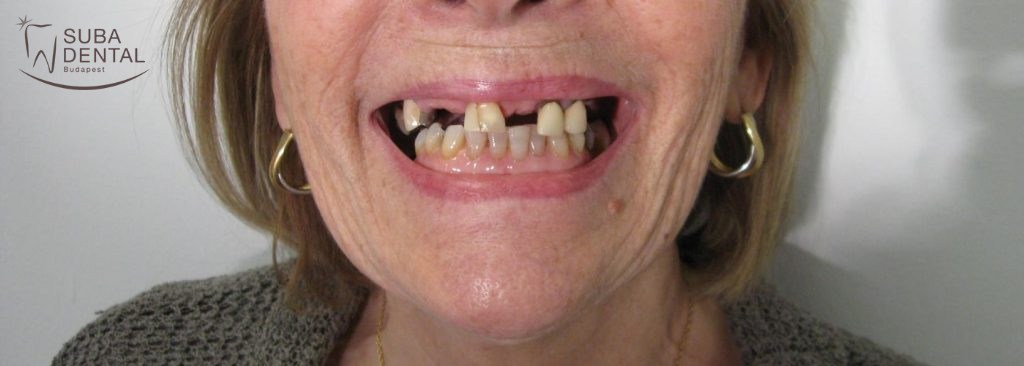

74 éves nő páciensünk a következő panaszokkal, illetve kérésekkel fordult a Suba Dentál rendelőhöz:

- Felső fogai közül jó néhányat elvesztett, és egy kapcsos fogsort készítettek a számára, melyet nem tudott megszokni.

- Esztétikusabb, fix pótlást szeretne.

- Örülne, ha fogai fehérebbek lennének.

- Az implantátumok beültetésétől nem zárkózik el, de a csontpótlástól idegenkedik.

Régi, kivehető felső fogsora, mellyel sosem tudott megbarátkozni